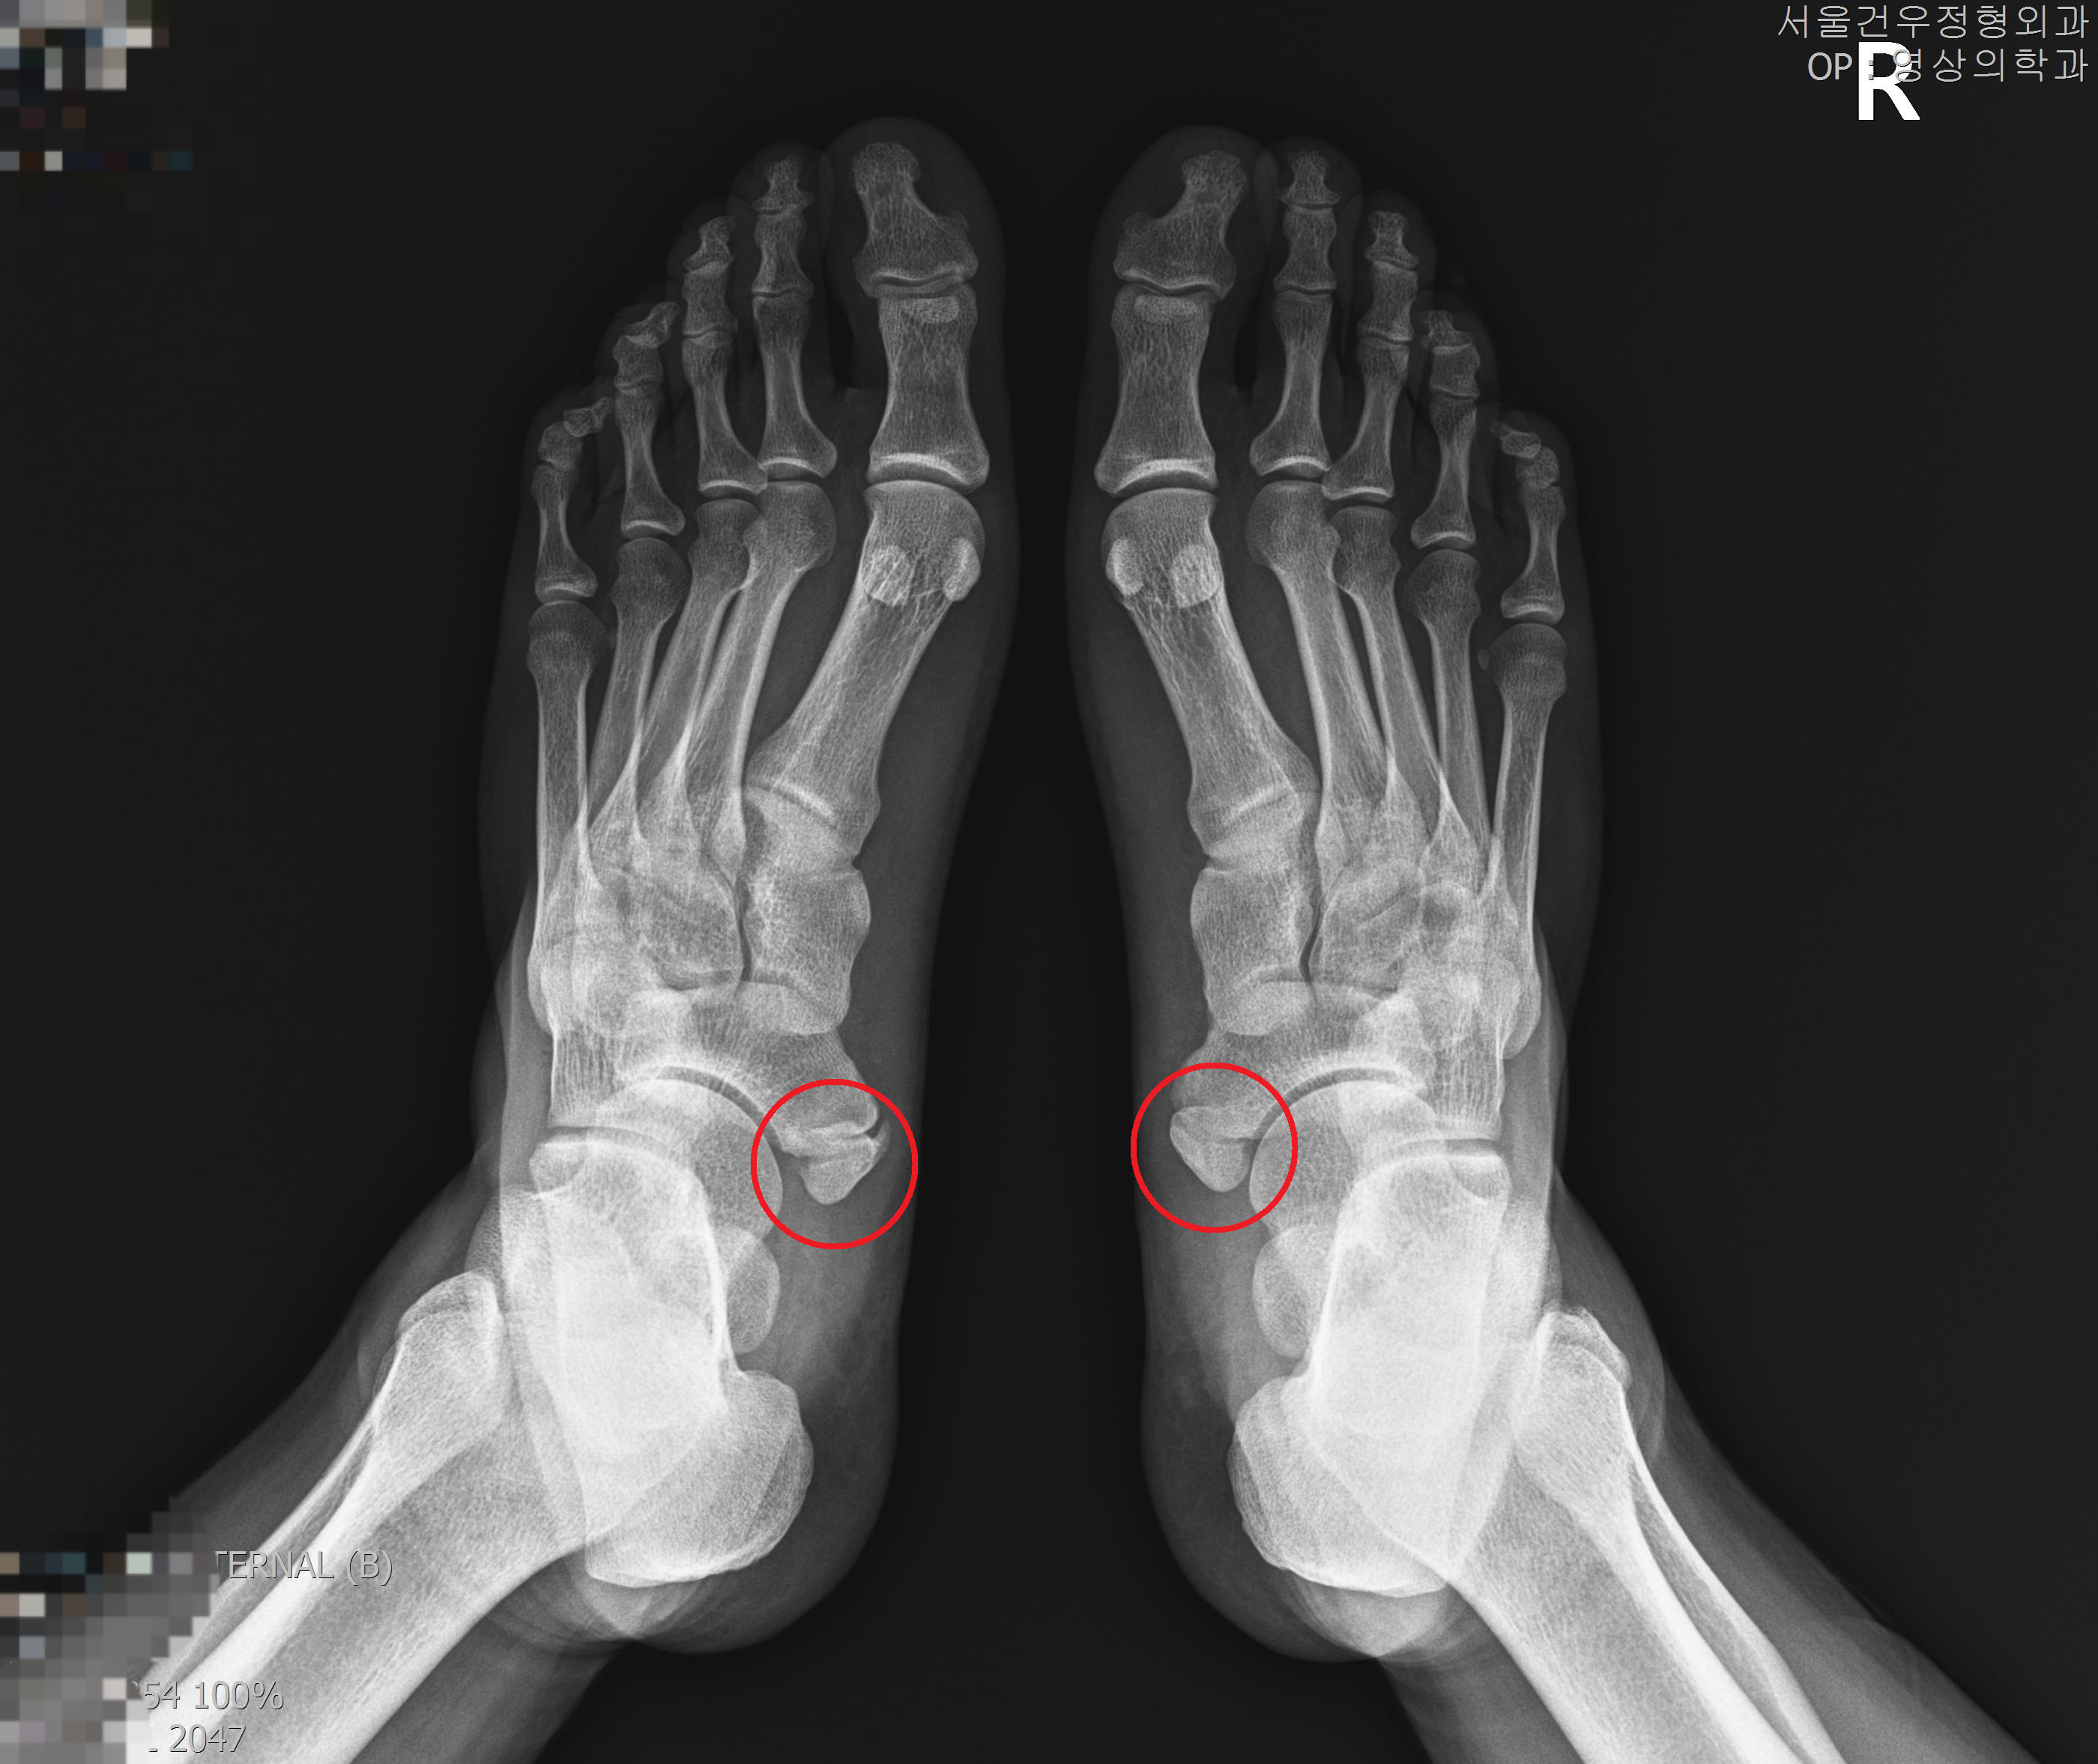

부주상골증후군치료 수술적/비수술적 치료방법은?